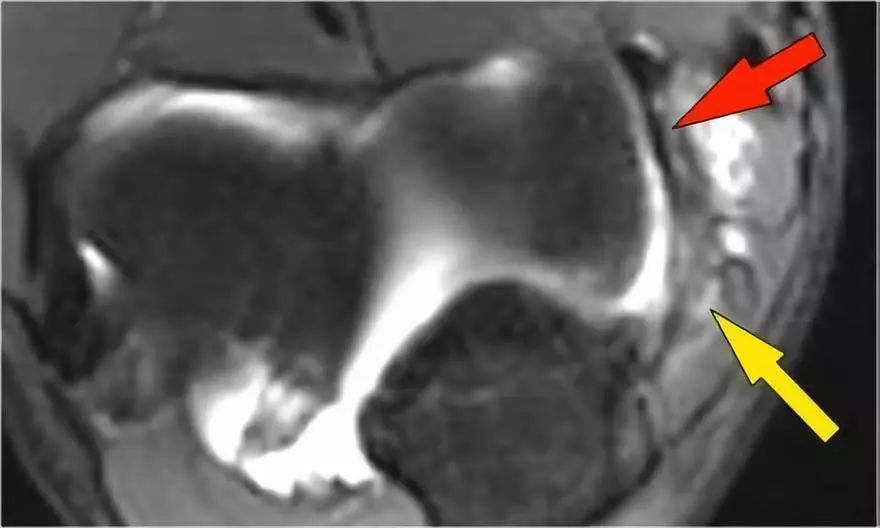

外翻过度综合征的关节病由于外翻过载,在肱骨-尺骨关节的后内侧部分存在剪切力。注意在T1W图像上看到的软骨下硬化(红色箭头)。在T2W图像上存在软骨下骨髓水肿和软骨损失(黄色箭头)。

冠状图像上有一个美丽的UCL前束,但注意到关节内侧部分有骨赘形成(红色箭头)。当我们按照顺序向下看,可以看到存在一小部分低信号强度(黄色箭头),这是UCL的一部分撕裂。